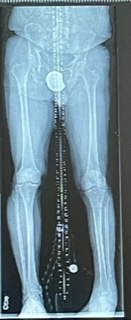

I was born with a birth defect, a left clubfoot. My right foot is normal. My parents took me to several specialists when I was a child. The decision was made to not do anything surgically to my left foot. The doctors told my parents to let me do anything I wanted but when my left foot started to hurt just stop that activity and let the foot recover. I followed this advice for 61 years.

By the end of 2021, I was feeling a lot of pain in my left foot and ankle after approximately 4-5 hours of use. The foot became extremely inverted, so walking was getting difficult. Working in the yard and home do-it-yourself projects, activities I love, became hard. I had no confidence in my ability to get around enough to get the jobs done.

There is severe acquired no varus deformity and metatarsus adductus and metatarsus varus. There is severe varus alignment of the ankle. There is lateral subluxation of the talus with respect to the tibia. There is bone-on-bone apposition of the medial aspect of the articular surface the talus with the lateral aspect of the articular surface of the tibia. There is apposition of the medial process of the talus with the medial malleolus. There is prominent cystic change in the medial malleolus and sclerosis of the medial process of talus. There is narrowing of the subtalar joint. There is fibular impingement with impingement of the lateral malleolus with a posterior aspect of the talus. There is a chronic nonunion of a fracture of the base of the 5th metatarsal with a bony fragment measuring about 16 mm beneath the base of the 5th metatarsal.